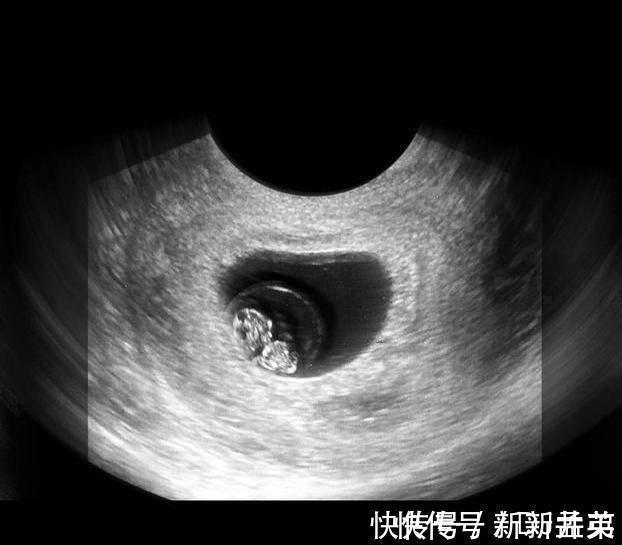

在上图可见是个双胎妊娠,胎儿具有一个很大的头,和身材很不对称,是不是跟出生后的胎宝宝有点像了?其实此时的头部比例更悬殊,宝宝的额面部器官发育很明显,心脏也开始了跳动,出现了胎心,此时做B超,可见胎心胎芽。